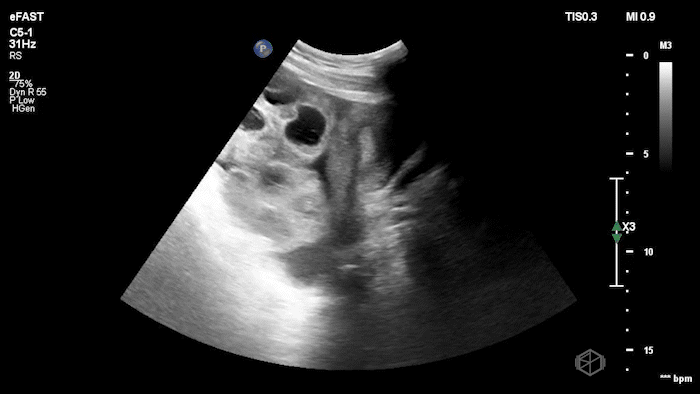

Dr.’s Konner and Maher scanned the patient and saw the following:

Initially it appears as though there is anechoic material above the liver and it does seem to make sharp angles. However, Dr. Konner and Dr. Maher utilized color doppler to evaluate the area and noted that it was simply the inferior vena cava. The patient ultimately had a CT scan that demonstrated no emergent findings.

Diagnosis: Potential false positive FAST - Inferior Vena Cava as a mimic of Free Fluid.

• Vessels can mimic free fluid. The IVC and other vascular structures sit right where we look for RUQ fluid and may appear anechoic in a single still frame. Use color doppler when not sure, free fluid will most commonly be at the caudal liver tip, and rarely just above the spine where the IVC sits.

• Always identify known landmarks (diaphragm, liver edge, kidney, spine) in RUQ views. If you see an anechoic region, ask: Does this structure have sharp, well-defined walls (suggesting a vessel)? Does it run longitudinally/continuously (vessel) or is it pooling between structures (free fluid)?